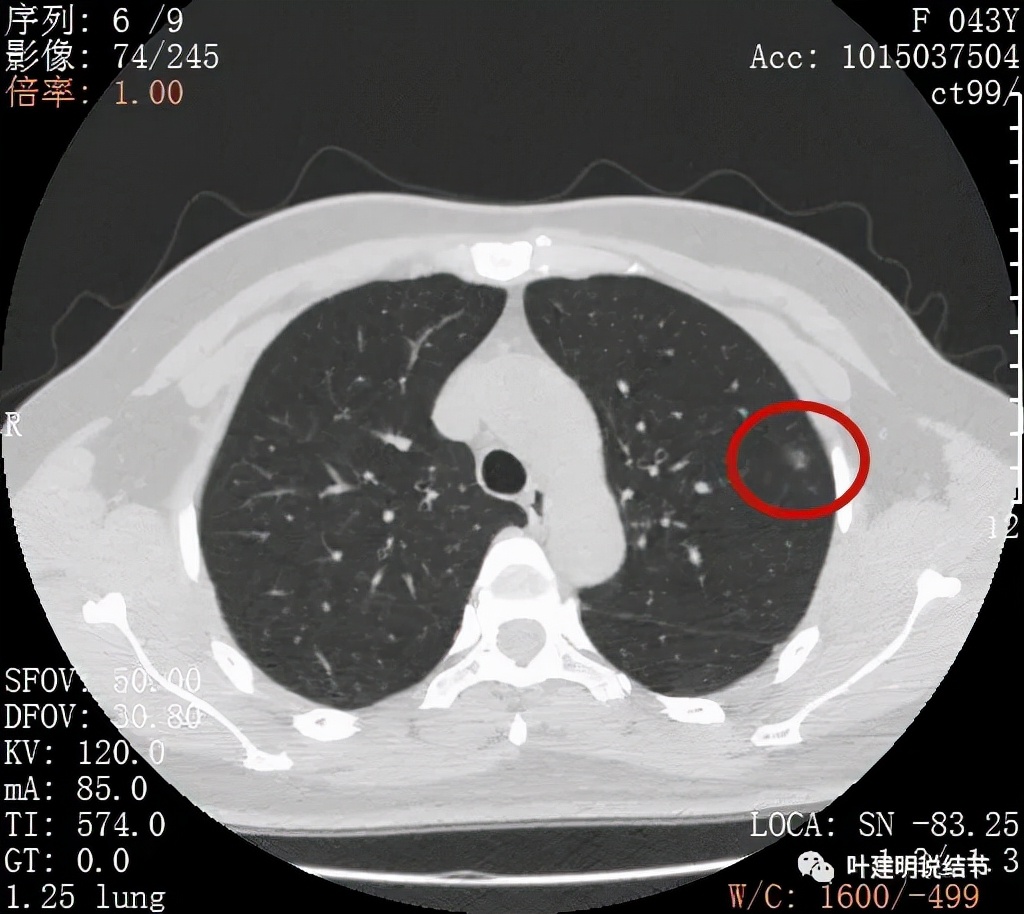

病灶密度较低,膨胀性略,瘤肺边界在靶扫描上还是显得有些清晰的

病灶瘤肺边界清,密度偏低,有点散,但有微小血管进入(桔色箭头)

病灶整体密度较低,但轮廓较清,内部密度不大均匀,显得杂乱

不均质的偏低密度磨玻璃结节,轮廓清